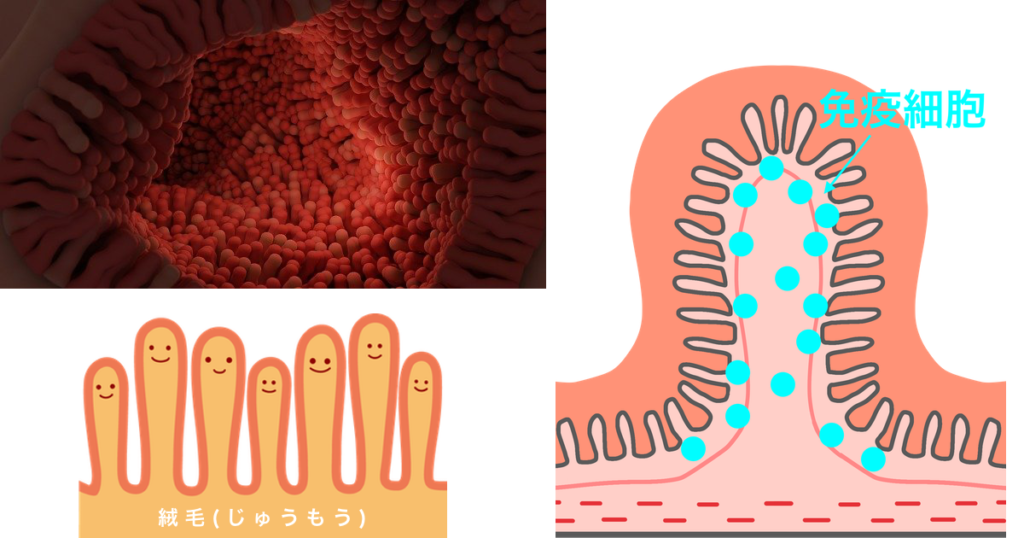

腸の働きで、栄養素を吸収や消化吸収を助けることは、皆さんよくご存知だと思います。しかし、病原菌を排除するイメージはあまりないと思います。

腸の壁は、絨毛と呼ばれる多くの突起物に覆われ、その中に免疫細胞があります。細菌やウィルスがやってくると免疫細胞がやっつけてくれます。NK細胞はがん細胞を食べちゃう細胞です。

免疫細胞のお話

暴走する免疫細胞

私たちの腸には免疫細胞(マクロファージ、Tレグ細胞、Bリンパ球、NK細胞)がありますが、暴走してしまうことがあります。これが本当に始末に悪いんですね〜。味方まで攻撃して手に追えなくなってしまいます。